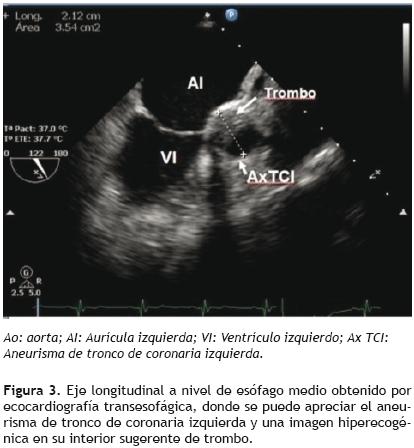

En abril del 2007, se valoró nuevamente con ecocardiograma transtorácico y transesofágico observándose el aneurisma del tronco de coronaria izquierda sin cambios con respecto a estudios previos (Figura 3). En una nueva valoración, aproximadamente un año después, se practicó una tomografía computarizada de control, en la cual no se observa crecimiento del aneurisma, así como tampoco se encuentran datos sugerentes de ruptura del mismo (Figura 4). Además, se realizó la evaluación del aneurisma de tronco con ecocardiograma tridimensional (Figura 5).